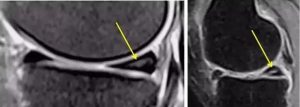

下图II级